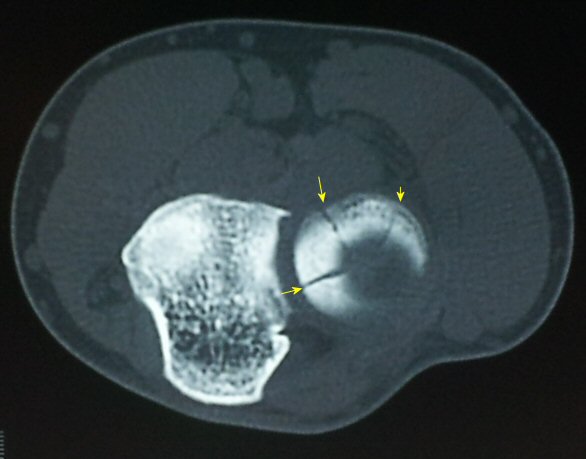

°ËÇ»ÅÍ ÃÔ¿µ : ¿ä°ñ µÎ ÀåÃà¸é °ñÀý( ±×¸² 6. 7)

1) ¿ä°ñµÎ¿Í ¿ä°ñ °æ°èºÎÀÇ ¿¹°¢À¸·Î ÀÌÇà

2) ¿ä°ñµÎ ÇÇÁú°ñÀÇ ºÒ±ÔÄ¥º¯È­

3) ¿ä°ñµÎ¿Í ¿ä°ñ °æ°èºÎ¿¡ ¼ö¾× Àú·ù

4) ¾Æ·§ÆÈÀ» µ¹¸®¸é¼­ ¿ä°ñµÎ Àüü¸¦ È®ÀÎÇÏ¿© ¿ä°ñµÎ ÀåÃà¸é°ñÀý È®ÀÎ